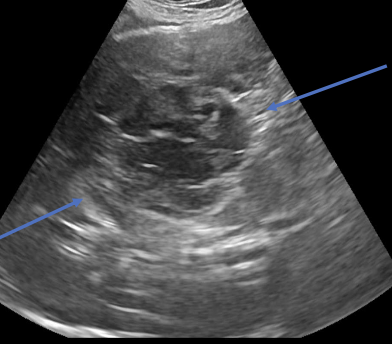

what is the appearance of hemangiosarcoma lesions in the abdomen using abdominal ultrasound?

-heterogenous (hypoechoic to targetoid to mixed)

-cavitation

- +/- peritoneal effusion